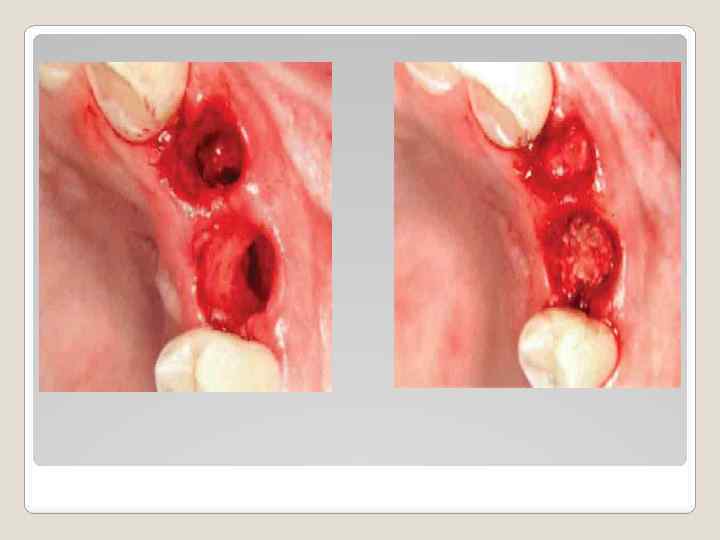

Профилактика атрофии альвеолярного отростка с помощью материала Easy-graft ® во фронтальном участке верхней челюсти (клинический случай). В клинику обратился пациент – мужчина в возрасте 38 лет, с жалобами на отлом коронковой части 23 зуба, подвижность 22 зуба и болезненность при надкусывании в этой области верхней челюсти. 22 зуб, пролеченный эндодонтически, имел 2 степень подвижности. И в проекции верхушки корня на слизистой оболочке был расположен свищ, из которого поступало гнойное выделение. 23 зуб был сломан на 3 мм ниже уровня десны и демонстрировал открытый канал корня зуба (Фото 1). При рентгенологическом обследовании были диагностированы две кисты в апикальных участках 22 и 23 зубов каждая размером около 10 мм в диаметре. Резорбция костной ткани начиналась в районе средней трети корней зубов (Фото 2).

После диагностики при определении плана лечения было установлено, что 22 зуб и корень 23 не подлежат восстановлению. Эти зубы должны быть удалены и одновременно должно быть проведено удаление обеих кист. Соседние зубы абсолютно здоровы, следовательно реабилитацию больного необходимо завершить изготовлением двух металокерамических коронок, опирающихся на имплантаты. 22 зуб и оставшийся корень 23 зуба были атравматично удалены с применением периотомов и элеваторов. Был произведен глубокий кюретаж лунок оставшихся корней и удалены все грануляционные ткани и оболочки кист (Фото 3). Для профилактики атрофии альвеолярного отростка после удаления корней зубов и цистэктомии костный дефект был заполнен материалом Easy Graft® 400 (3 шприца, общее количество материала составило 1. 2 мл). (Фото 4). Материал имеет очень большое преимущество по сравнению с другими материалами. Попадая в контакт с жидкостью раны, он начинает твердеть и хорошо стабилизирует костные стенки дефекта. После хорошего уплотнения материала в лунках удаленных корней с расположением его на 0. 5 мм ниже уровня кости, края ран были адаптированы и был установлен временный протез. В данной методике, благодаря свойству материала твердеть в присутствии жидкости, защитная мембрана не используется и нет необходимости плотного закрывания дефекта мягкими тканями.